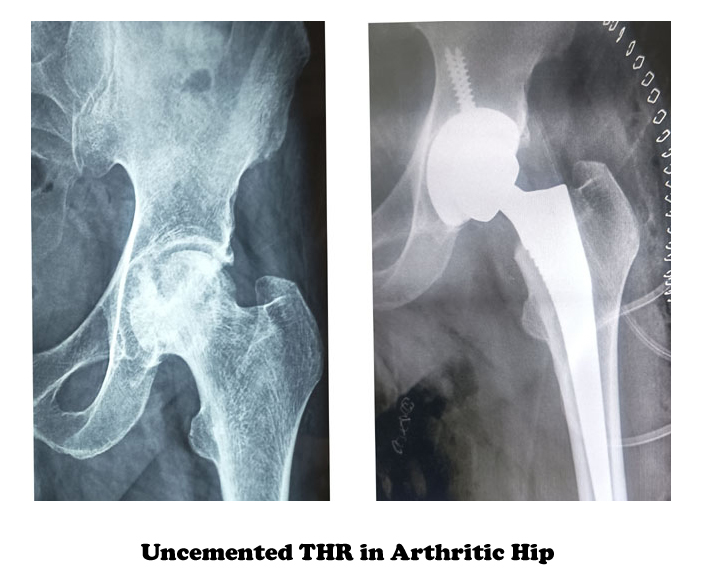

The parts used to replace the joint are the same and come in two general varieties: cemented and uncemented Cemented parts are fastened to healthy bone with a special glue or cement.

Hip replacement using these parts is referred to as a “cemented” procedure. Uncemented parts rely on a process called biologic fixation, which holds them in place.

This means that the parts are made with a porous surface that allows your own bone to grow into the pores and hold the new parts in place. Sometimes a doctor will use a cemented femur part and uncemented acetabular part. This combination is referred to as a hybrid replacement.

Cemented replacements are more frequently used for older, less active people and people with weak bones, such as those who have osteoporosis, while uncemented replacements are more frequently used for younger, more active people.